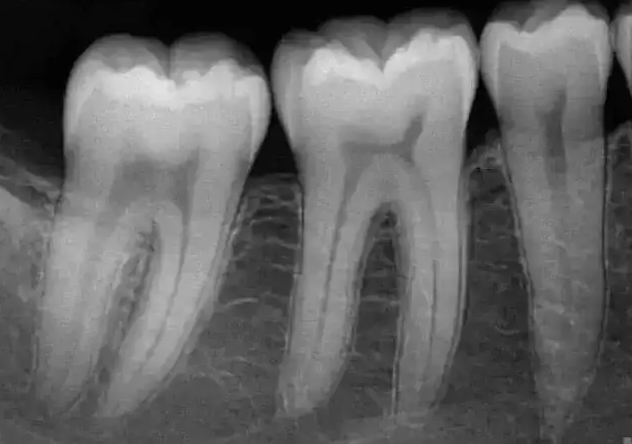

口腔设备有什么一文读懂 | 口腔影像设备大科普,哪种才是最适合你的选择?_https://www.jmylbn.com_新闻资讯_第5张

▲牙片图像

牙片机使用方便快捷,能较为清楚地显示牙冠牙根,经常用于简单的牙齿检查如龋齿、牙根断裂、牙根囊肿以及检查补牙、根管治疗的效果等。